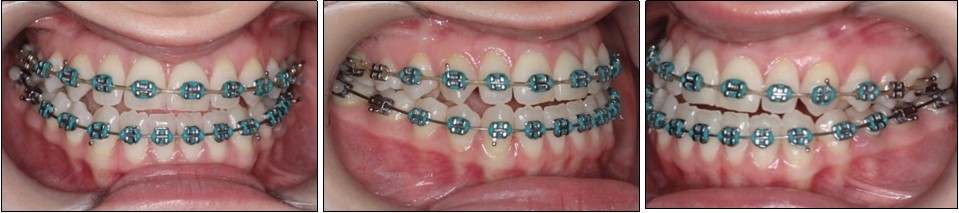

Post-surgical orthodontic treatment was started 4 weeks after the surgery. Wearing of bilateral box elastics was recommended in order to improve interdigitation. (Figure 6) The orthodontic treatment was finished on 0.019x0.025 SS archwires. Post-surgery cephalometric analysis revealed an increase in SNA value by 4 degrees (SNA 82 degrees) and a decrease in SNB value also by 4 degrees (SNB 79 degrees). The patient was now in a skeletal class I, with ANB 3 degrees. An examination of the soft tissue on the radiograph reveales a better relation between the upper and lower lip. (Figure 7).

Figure 6.Post-surgical intraoral photographs, with bilateral box elastics

Post-surgical intraoral photographs, with bilateral box elastics